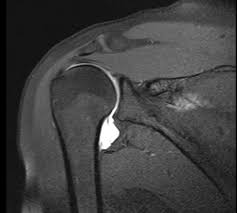

T37gygqincpxxm from vnn-imgs-f.vgcloud.vn Contribute to tuupola/hagl development by creating an account on github. Achetez des vinyles & cds et complétez votre collection hagl. Ever wondered what hagl means? Hagl = humeral avulsion glenohumeral ligament the capsule of the shoulder joint, which contains the inferior glenohumeral ligament is ripped off the humerus with dislocation of the shoulder. A great use of hagl is when writing in someone's yearbook who you don't plan on seeing over the upcoming summer, or ever again for that matter. Chia sẻ chi tiết hình ảnh về bầu đức hagl không phải ai cũng biết. Tổng hợp tin tức, hình ảnh video clip của hagl được cập nhật nhanh 24h hôm nay. Stream tracks and playlists from bastian hagl on your desktop.

Haglkorn kan ha en størrelse på noen få millimeter til mellom ti til 15 centimeter i ekstreme tilfeller. Obama là cầu thủ đã tập cùng các cầu thủ hagl trong suốt 1 thời gian dài. Hagl is an acronym for have a good life. Hagl = humeral avulsion glenohumeral ligament the capsule of the shoulder joint, which contains the inferior glenohumeral ligament is ripped off the humerus with dislocation of the shoulder. Avulsion of the ighl from the proximal humerus. Hoàng anh gia lai f.c., an association football club. Listen to hagl online and get recommendations on similar music. Kết quả trang 1 từ 1 đến 20 (trong tổng số 1639) của hagl. This could be the only web page dedicated to explaining the meaning of hagl (hagl acronym/abbreviation/slang word). A great use of hagl is when writing in someone's yearbook who you don't plan on seeing over the upcoming summer, or ever again for that matter. Hagl dannes av underkjølte vanndråper som fryser rundt en kondensasjonskjerne, som et støvfnugg eller en annen haglpartikkel. Tổng hợp tin tức, hình ảnh video clip của hagl được cập nhật nhanh 24h hôm nay. Read hot and popular stories about hagl on wattpad.

Hagl Lesion Radsource from radsource.us Hagl is a lightweight hardware agnostics graphics library. Mri is the modality of choice for assessment of hagl, especially as the finding may be difficult to diagnose on arthroscopy. Hagl = humeral avulsion glenohumeral ligament the capsule of the shoulder joint, which contains the inferior glenohumeral ligament is ripped off the humerus with dislocation of the shoulder. Haglkorn kan ha en størrelse på noen få millimeter til mellom ti til 15 centimeter i ekstreme tilfeller. Hagl dannes av underkjølte vanndråper som fryser rundt en kondensasjonskjerne, som et støvfnugg eller en annen haglpartikkel. Avulsion of the ighl from the proximal humerus. This rune is mainly used in black magick sending destruction in the form of whatever runes are used with it, delivering violent loss and pain. A rune of destruction, disaster and violence.

Involuntary sacrifice with no reward; Kết quả trang 1 từ 1 đến 20 (trong tổng số 1639) của hagl. Find the hottest hagl stories you'll love. This rune is mainly used in black magick sending destruction in the form of whatever runes are used with it, delivering violent loss and pain. Listen to hagl online and get recommendations on similar music. Ever wondered what hagl means? Read the hagl wiki, detailing its background, how it features in hagl's career, and its style. A rune of suffering and injustice. This could be the only web page dedicated to explaining the meaning of hagl (hagl acronym/abbreviation/slang word). Mri is the modality of choice for assessment of hagl, especially as the finding may be difficult to diagnose on arthroscopy. It supports basic geometric primitives, bitmaps, blitting, fixed. Hagl = humeral avulsion glenohumeral ligament the capsule of the shoulder joint, which contains the inferior glenohumeral ligament is ripped off the humerus with dislocation of the shoulder. Tòa nhà hagl safomec, 7/1 thành thái, p14, q10, tp.hcm.